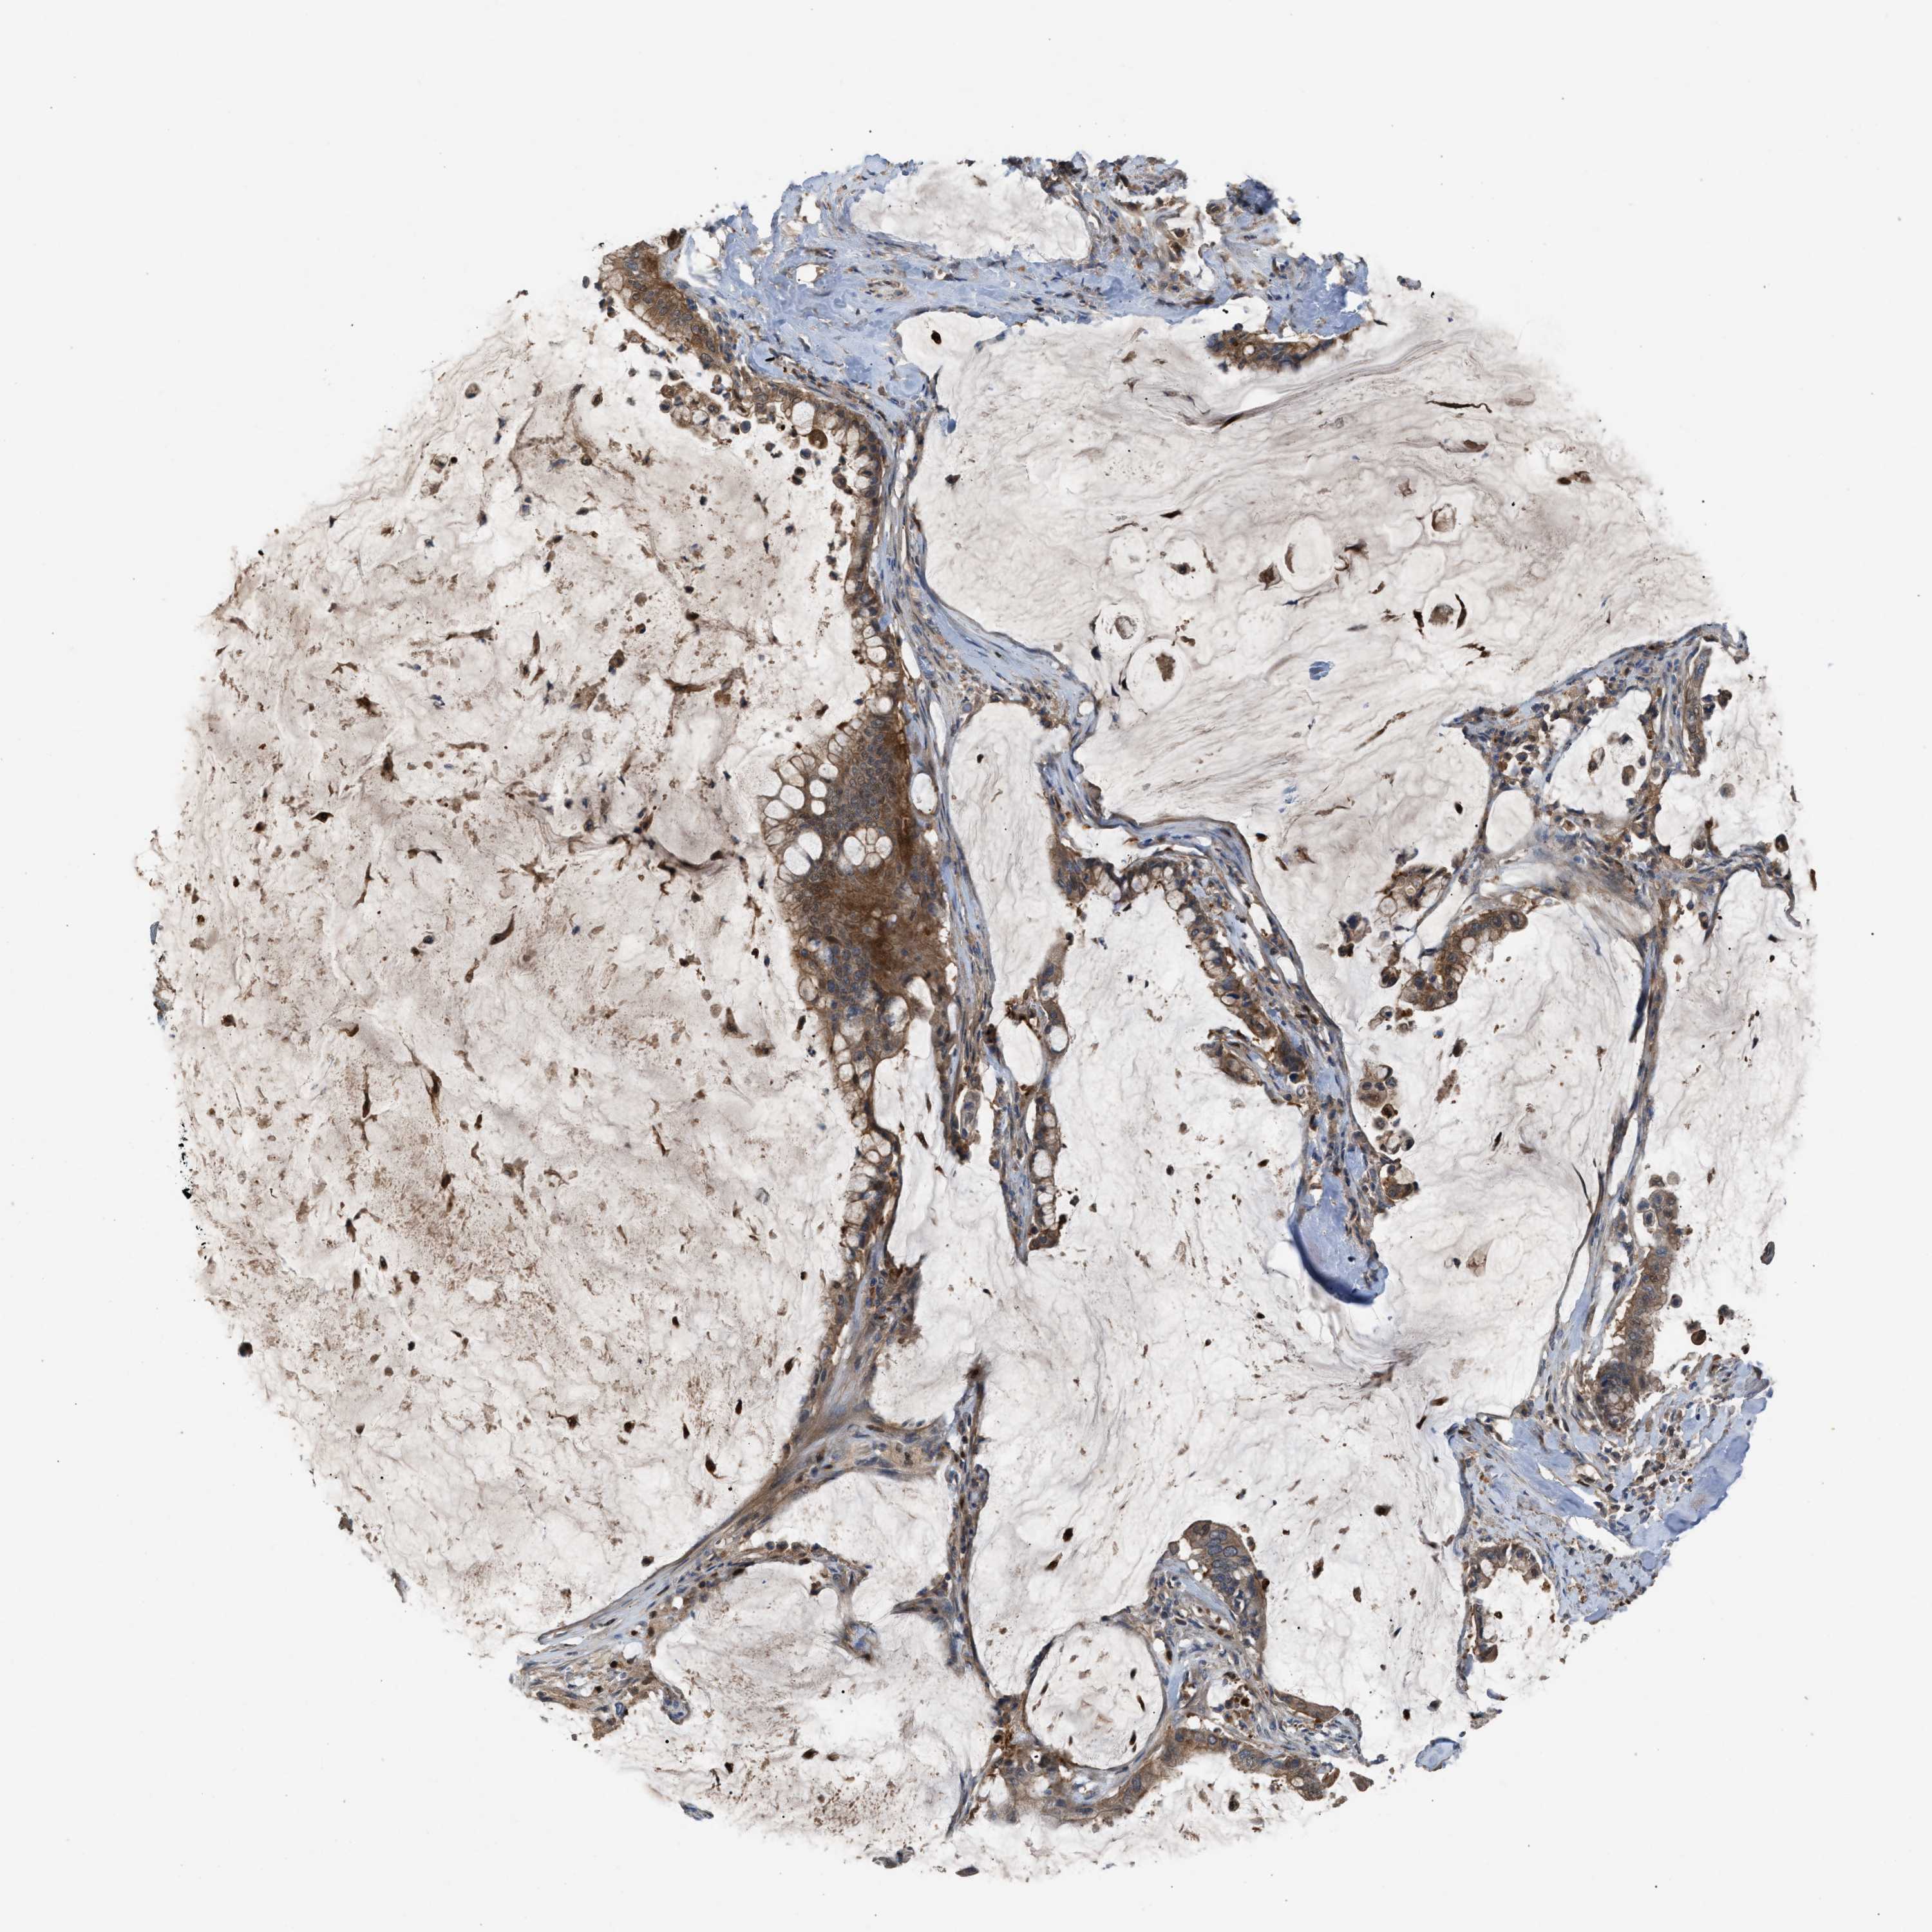

PANCREATIC CANCER - Protein expressioni

A mouse-over function shows sample information and annotation data. Click on an image to view it in a full screen mode. Samples can be filtered based on level of antibody staining by selecting one or several of the following categories: high, medium, low and not detected. The assay and annotation is described here.

Note that samples used for immunohistochemistry by the Human Protein Atlas do not correspond to samples in the TCGA dataset.

Antibody stainingi

Antibody staining in the annotated cell types in the current human tissue is reported as not detected, low, medium, or high, based on conventional immunohistochemistry profiling in selected tissues. This score is based on the combination of the staining intensity and fraction of stained cells.

Each image is clickable and will lead to virtual microscopy that enables deeper exploration of all samples and also displays staining intensity scores, fraction scores and subcellular localization as well as patient and tissue information for each sample.

Antibody HPA021545

Antibody HPA021849

Staining

High

Medium

Low

Not detected

Intensity

Strong

Moderate

Weak

Negative

Quantity

>75%

75%-25%

<25%

None

Location

Nuclear

Cytoplasmic/membranous

Cytoplasmic/membranous,nuclear

Adenocarcinoma, NOS